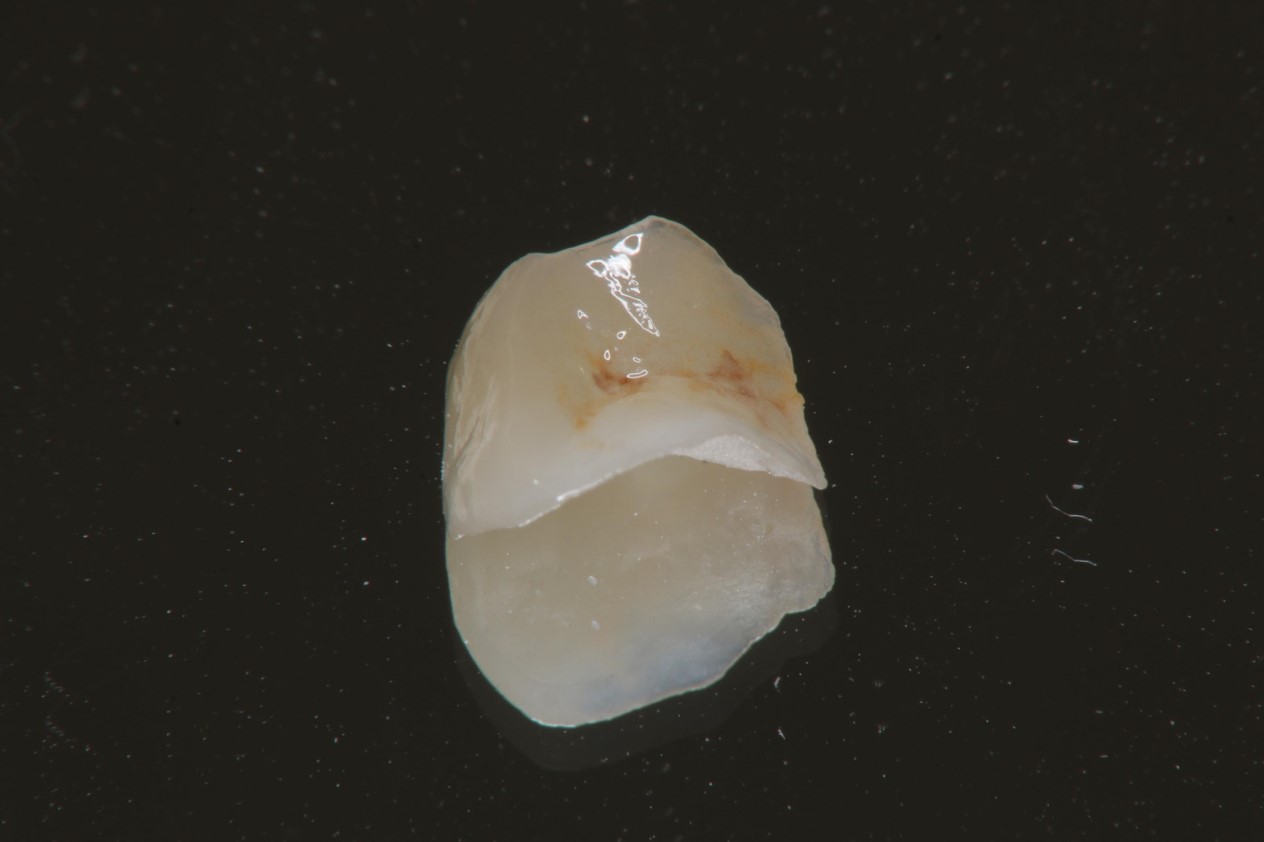

陶瓷崁體